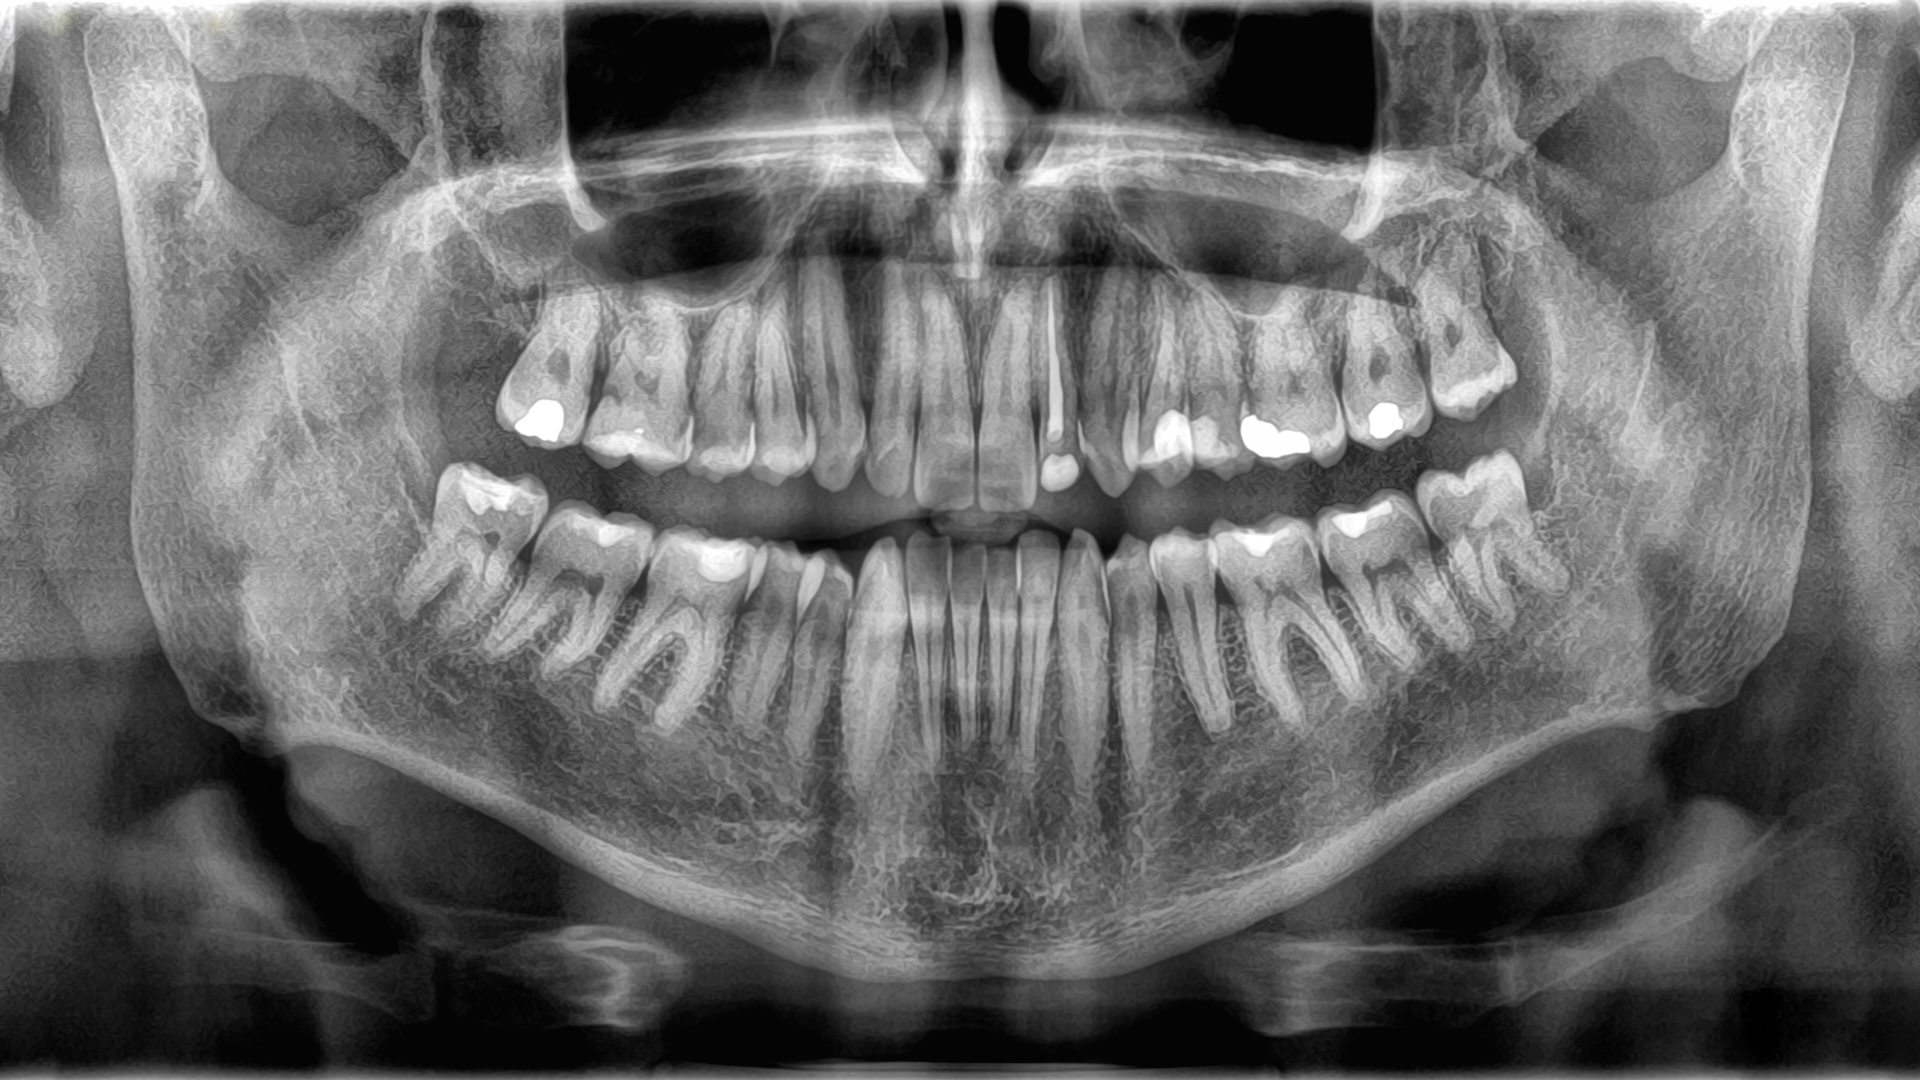

While often grouped, bones and teeth possess distinct structural designs, a direct reflection of their differing biological roles. Encasing each tooth is enamel, a remarkably thin layer of mineralized tissue. This isn’t just any protective coating; enamel holds the title of the human body’s hardest substance. Its exceptional durability is attributed to a densely packed crystalline matrix, formed from a potent compound of calcium and phosphate.

Beneath the tooth’s resilient outer layer of enamel, a robust mineralized tissue known as dentin forms the majority of its structure. While slightly less hard than enamel, dentin provides substantial strength and is crisscrossed by microscopic tubules that accommodate tiny blood vessels and nerve endings. Deeper still, at the tooth’s very core, resides the pulp. This soft, jelly-like substance is a vital hub, brimming with blood vessels that supply essential nutrients and a dense network of nerves responsible for sensory perception, effectively controlling the tooth’s ability to feel.

The intricate structure of human bones begins with their outermost layer: the periosteum. This remarkably thin yet exceptionally tough membrane serves as a vital protective sheath, housing the essential blood vessels and nerves critical for both bone growth and the intricate process of healing.

Immediately beneath this crucial outer covering lies the durable compact bone tissue. This dense and unyielding layer is celebrated for its immense strength and provides the primary structural support for the skeletal system.

Venturing deeper, the bone’s internal architecture transforms into a honeycomb-like network known as cancellous tissue. This sponge-like substance, perforated with numerous tiny cavities, serves as the essential reservoir for bone marrow—the body’s vital production factory for new blood cells.

A fundamental biological distinction sets bones apart from teeth. Bones are living tissues, clearly evidenced by the intricate network of nerves and blood vessels that permeate both their interior and exterior. In contrast, teeth are not living tissues and consequently lack this vital neurological and vascular supply, marking a crucial difference in their physiological makeup.